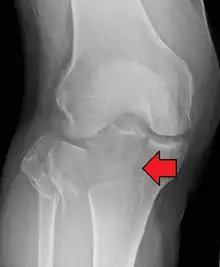

Fractures of the tibial plateau are caused by a varus (inwardly angulating) or valgus (outwardly angulating) force combined with axial loading or weight bearing on knee. The classically described situation in which this occurs is from a car striking a pedestrian's fixed knee (bumper fracture). A bumper fracture is usually a fracture of the lateral tibial plateau, caused by a forced valgus movement. This causes the lateral part of the distal femur and the lateral tibial plateau to come into contact, compressing the tibial plateau and causing the tibia to fracture. The name of the injury is because it was described as being caused by the impact of a car bumper on the lateral side of the knee while the foot is planted on the ground, although this mechanism is only seen in about 25% of tibial plateau fractures.[5] The term "bumper fracture" was coined in 1929 by Cotton and Berg.[6] Fracture of the neck of the fibula may also be found, and associated injury to the medial collateral ligament or cruciate ligaments occurs in about 10% of cases.[7][8]

In all injuries to the tibial plateau radiographs (commonly called x-rays) are imperative. Computed tomography scans are not always necessary but are sometimes critical for evaluating degree of fracture and determining a treatment plan that would not be possible with plain radiographs.[10] Magnetic Resonance images are the diagnostic modality of choice when meniscal, ligamentous and soft tissue injuries are suspected.[11][12] CT angiography should be considered if there is alteration of the distal pulses or concern about arterial injury.